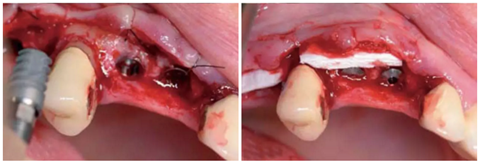

圖14:放置了3顆RatioPlant Avantgarde (HumanTech Germany)種植體。

圖15:放置Geistlich Mucograft®膠原基質(zhì)(Geistlich Pharma)來支撐軟組織。